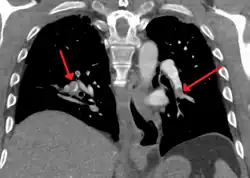

Large saddle embolus seen in the pulmonary artery (white arrows)

Fewer than 5 to 10% of symptomatic PEs are fatal within the first hour of symptoms.[38][92]